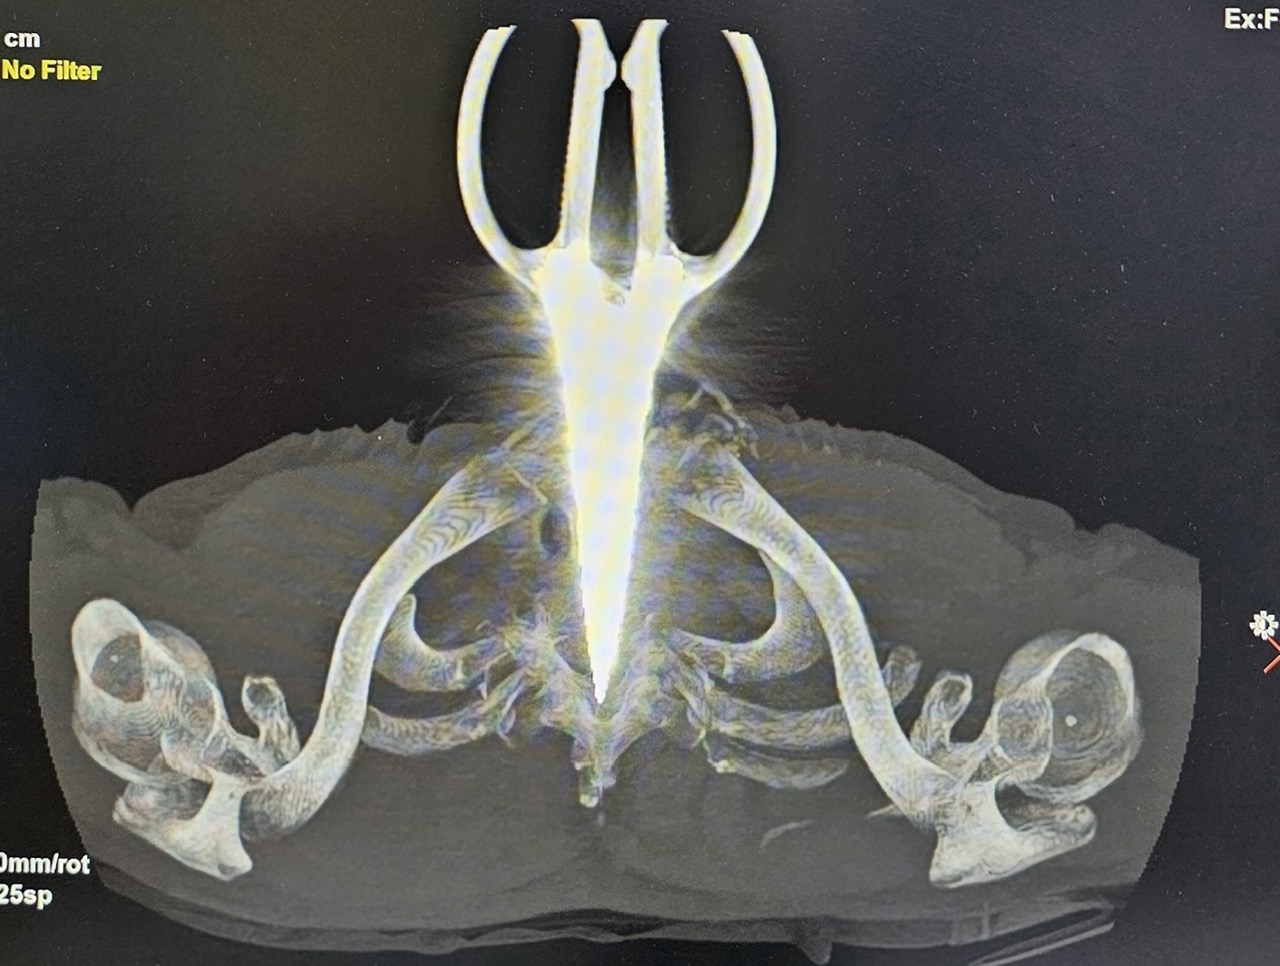

Imagem de uma tesoura cravada no pescoço de um homem.

Os resultados da radiografia e da tomografia computadorizada mostraram um corpo estranho metálico penetrando a porção média da vértebra torácica D1. O paciente foi encaminhado para cirurgia de emergência para remoção do corpo estranho e investigação da lesão medular.